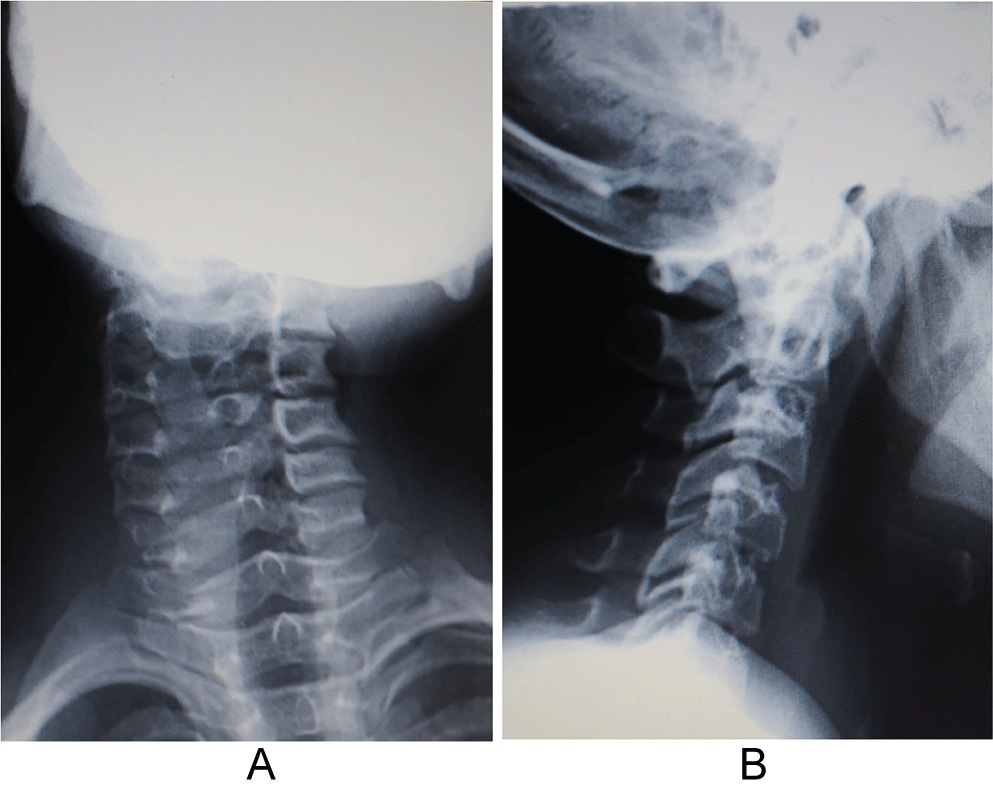

This patient study was approved by the Ethics Committee and was conducted following completion of the corresponding informed consent. A 10-year-old male patient in 2008 had consulted for a torticollis deformity that had originated during early childhood. This delay in first diagnosis is because patient is inmigrant and without diagnosis or previous treatment. Patient had classical deformities of torticollis: Shortening of SCM muscle, lateral inclination of the neck, smaller and higher eye, contralateral torsion with chin rising. Moreover, the patient also presented with a left-side facial deformity. The patient was not referred for any traumatic or infectious etiology of the oropharynx or for digestive or renal diseases. It was made a wide differential diagnosis, especially for to exclude nonmuscular causes of torticollis, presents in 18% of patients [1], Klippel-Feil anomalies (30%), posterior fossa tumors, syringomyelia or Arnold-Chiari malformation (51%) [1,2]. Additionally, neurologic exploration was done by a pediatric neurologist. Problems like dystonia, ataxia or abnormal deep tendon reflexes in upper and lower limbs did not exist. Also, osteocongenital neurological pathologies of the spinal cord and brain tumor were excluded by a pediatric neurologist. After these exclusions were made, we confirmed a diagnosis of inveterate congenital muscular torticollis. Preoperative studies, radiographic imaging, Computed Axial Tomography (CT) scans and Magnetic Resonance Imaging (MRI) of the cervical spine and skull (Figure1a, Figure 1b, Figure 2a, Figure 2b, Figure 3a, Figure 3b, Figure 4a, Figure 4b) highlighted Klippel-Feil Syndrome, fusion defects of the vertebral arches of the atlas, diastematomyelia and hypoplasia of the occipital condyles. CT images demonstrated, deformity of the anterior arch of the atlas was observed, consisting of hypoplasia of the right half and deformity and hypoplasia of the posterior arches C1 and C2 with concavity of the right posterior hemi-arch and convexity of the left arch, causing asymmetry of the spinal canal. Additionally, subluxation of the odontoid apophysis toward a right lateral mass of the atlas was observed (Figure 2a, Figure 3a). MRI showed deformity with extreme narrowing of the odontoid apophysis and irregular formation of the spinal canal with displacement of the spinal cord in the direction of the concavity of the torticollis (Figure 4a, Figure 4b). In 2009, unipolar distal tenotomy of the left SCM was performed, followed by orthotics and rehabilitation with notable improvement in cervical mobility but with minimal effect on facial asymmetry. In the 5-year postoperative CT and MRI, there were no significant changes in preoperative vertebral bone deformities, either visually or through the morphology of the spinal canal (Figure 5a, Figure 5b, and Figure 6).

Figure 1: Radiographs of the a) Anteroposterior; b) Lateral cervical spine. No anomalies of segmentation or rachischisis of the vertebral arches were observed. View Figure 1